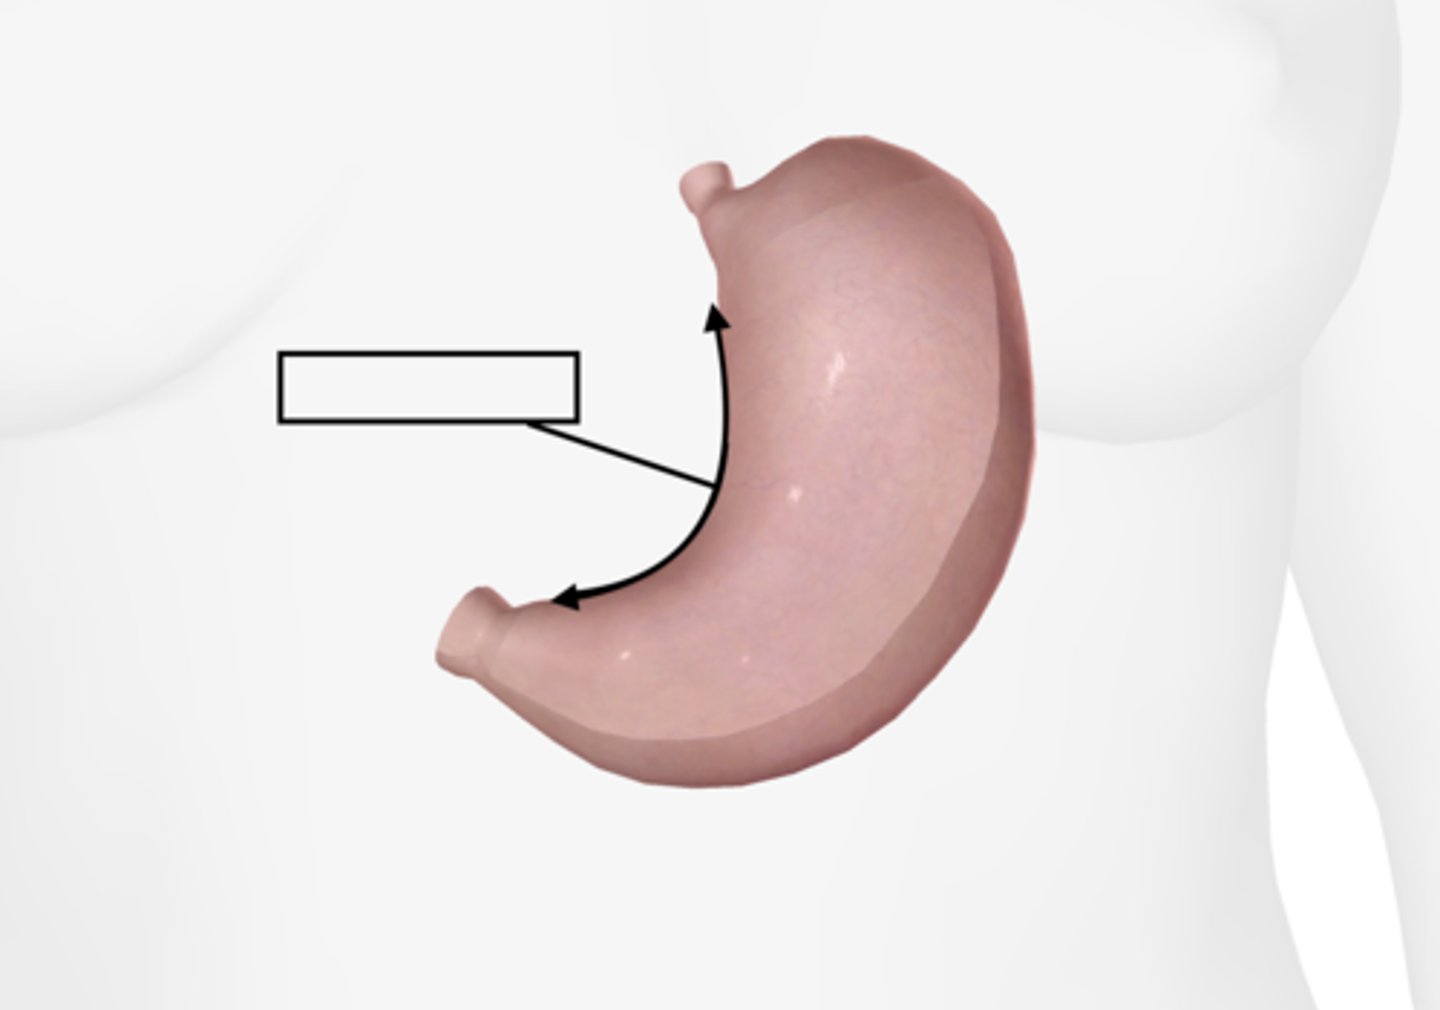

Stomach

Lesser curvature

Greater curvature

Cardiac sphincter

Pyloric sphincter